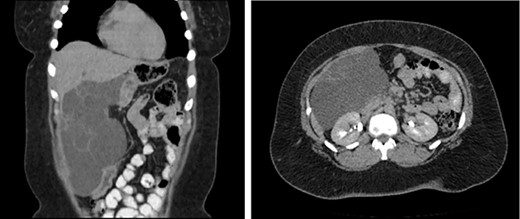

Computed tomography (CT) revealed a large multiloculated cystic lesion in segments IV and V of the liver measuring ~21.0 × 14.0 cm (Fig. 1). The mass extended down into the right lower quadrant, causing a mass effect with effacement of the duodenum, vena cava and displacement of the transverse and right colon inferiorly. Due to the recent nature of her cholecystectomy and cystic nature of the mass a biloma could not be excluded. Therefore a hepatobiliary iminodiacetic acid scan was ordered, which did exclude biloma.

CT of the abdomen and pelvis (coronal, axial) which reveals a septated complex cystic mass displacing the duodenum and vena cava.